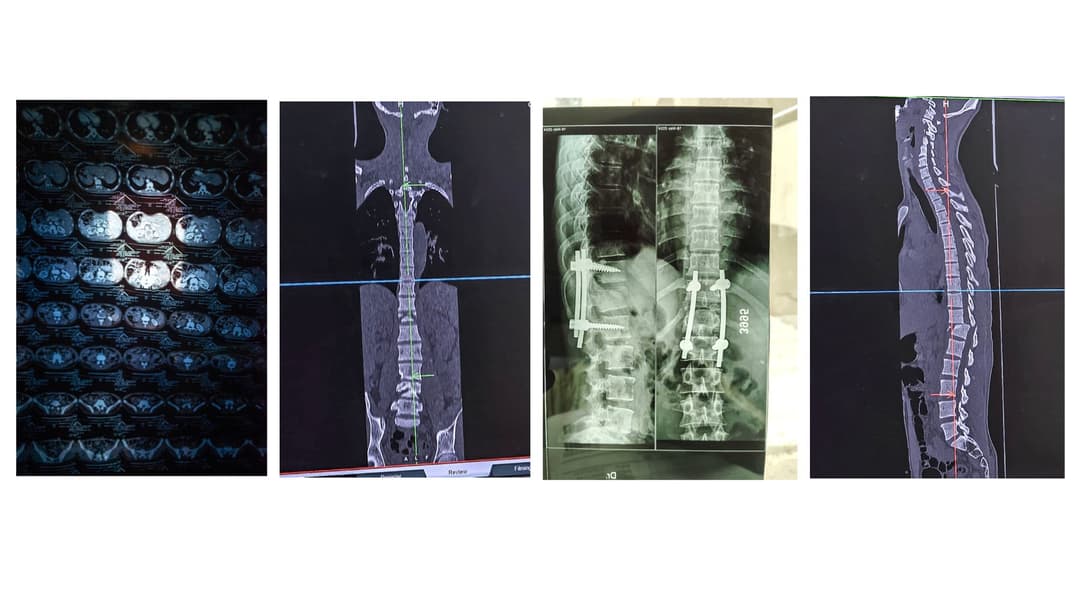

“Since that morning it’s been years of hospital visits,” says his father. VTHC doctors found that Arun had lost all power from waist down. His spinal cord had suffered critical damage. “They sent us to the Chamarajanagar Institute of Medical Sciences (CIMS). There, the doctors said his bone was jammed and he needed an operation. And a nerve was also cut. The hospital kept the reports. We were given medicines and injections,” says M. Sannarange Gowda.

After a surgery at the CIMS to fix the broken spinal canal and prevent further injury to the nerves, Arun returned to VTHC. There, the staff trained the primary caregivers in his family, including Arun’s young wife.